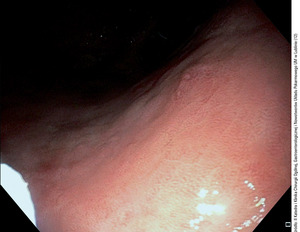

Wczesny rak przewodu pokarmowego definiowany jest jako nowotwór złośliwy pochodzenia nabłonkowego nieprzekraczający błony podśluzowej, bez cech naciekania błony mięśniowej właściwej. W przypadku wczesnego raka przełyku warunkiem rozpoznania jest wykluczenie obecności przerzutów do okolicznych węzłów chłonnych. Dokładność przedoperacyjnej oceny głębokości nacieku wczesnego raka oceniana jest na 70-95 proc. Wczesny rak może być widoczny jedynie jako zmiana zabarwienia błony śluzowej – częściej w postaci zaczerwienienia lub rzadziej – zblednięcia powierzchni. Szczególnie dotyczy to niewielkich zmian, trudnych do wykrycia w rutynowym badaniu (ryc.1). W przypadku znalezienia podejrzanej zmiany wskazane jest stosowanie barwień (płynem Lugola do nabłonka płaskiego lub indygokarminem albo błękitem metylenowym do nabłonka gruczołowego). Nowoczesne endoskopy wyposażone są w systemy powiększenia obrazu oraz systemy barwień elektronicznych oparte na oglądaniu zmian po podświetleniu ich wąską wiązką światła – (narrow band imaging NBI)(ryc. 2, 3).[2] Daje to możliwość dobrego uwidocznienia struktury powierzchni zmiany, jej granic oraz oceny rysunku naczyniowego, a co za tym idzie – wyboru optymalnego miejsca do pobrania wycinków. Tak precyzyjna ocena endoskopowa pozwala z ogromną dozą prawdopodobieństwa postawić jednoznaczne rozpoznanie, dlatego zwana jest też biopsją optyczną.[3] Tak więc decydujące znaczenie ma obraz endoskopowy: wielkość i kształt zmiany, jej typ makroskopowy określany wg klasyfikacji japońskich (ryc. 4).[4]